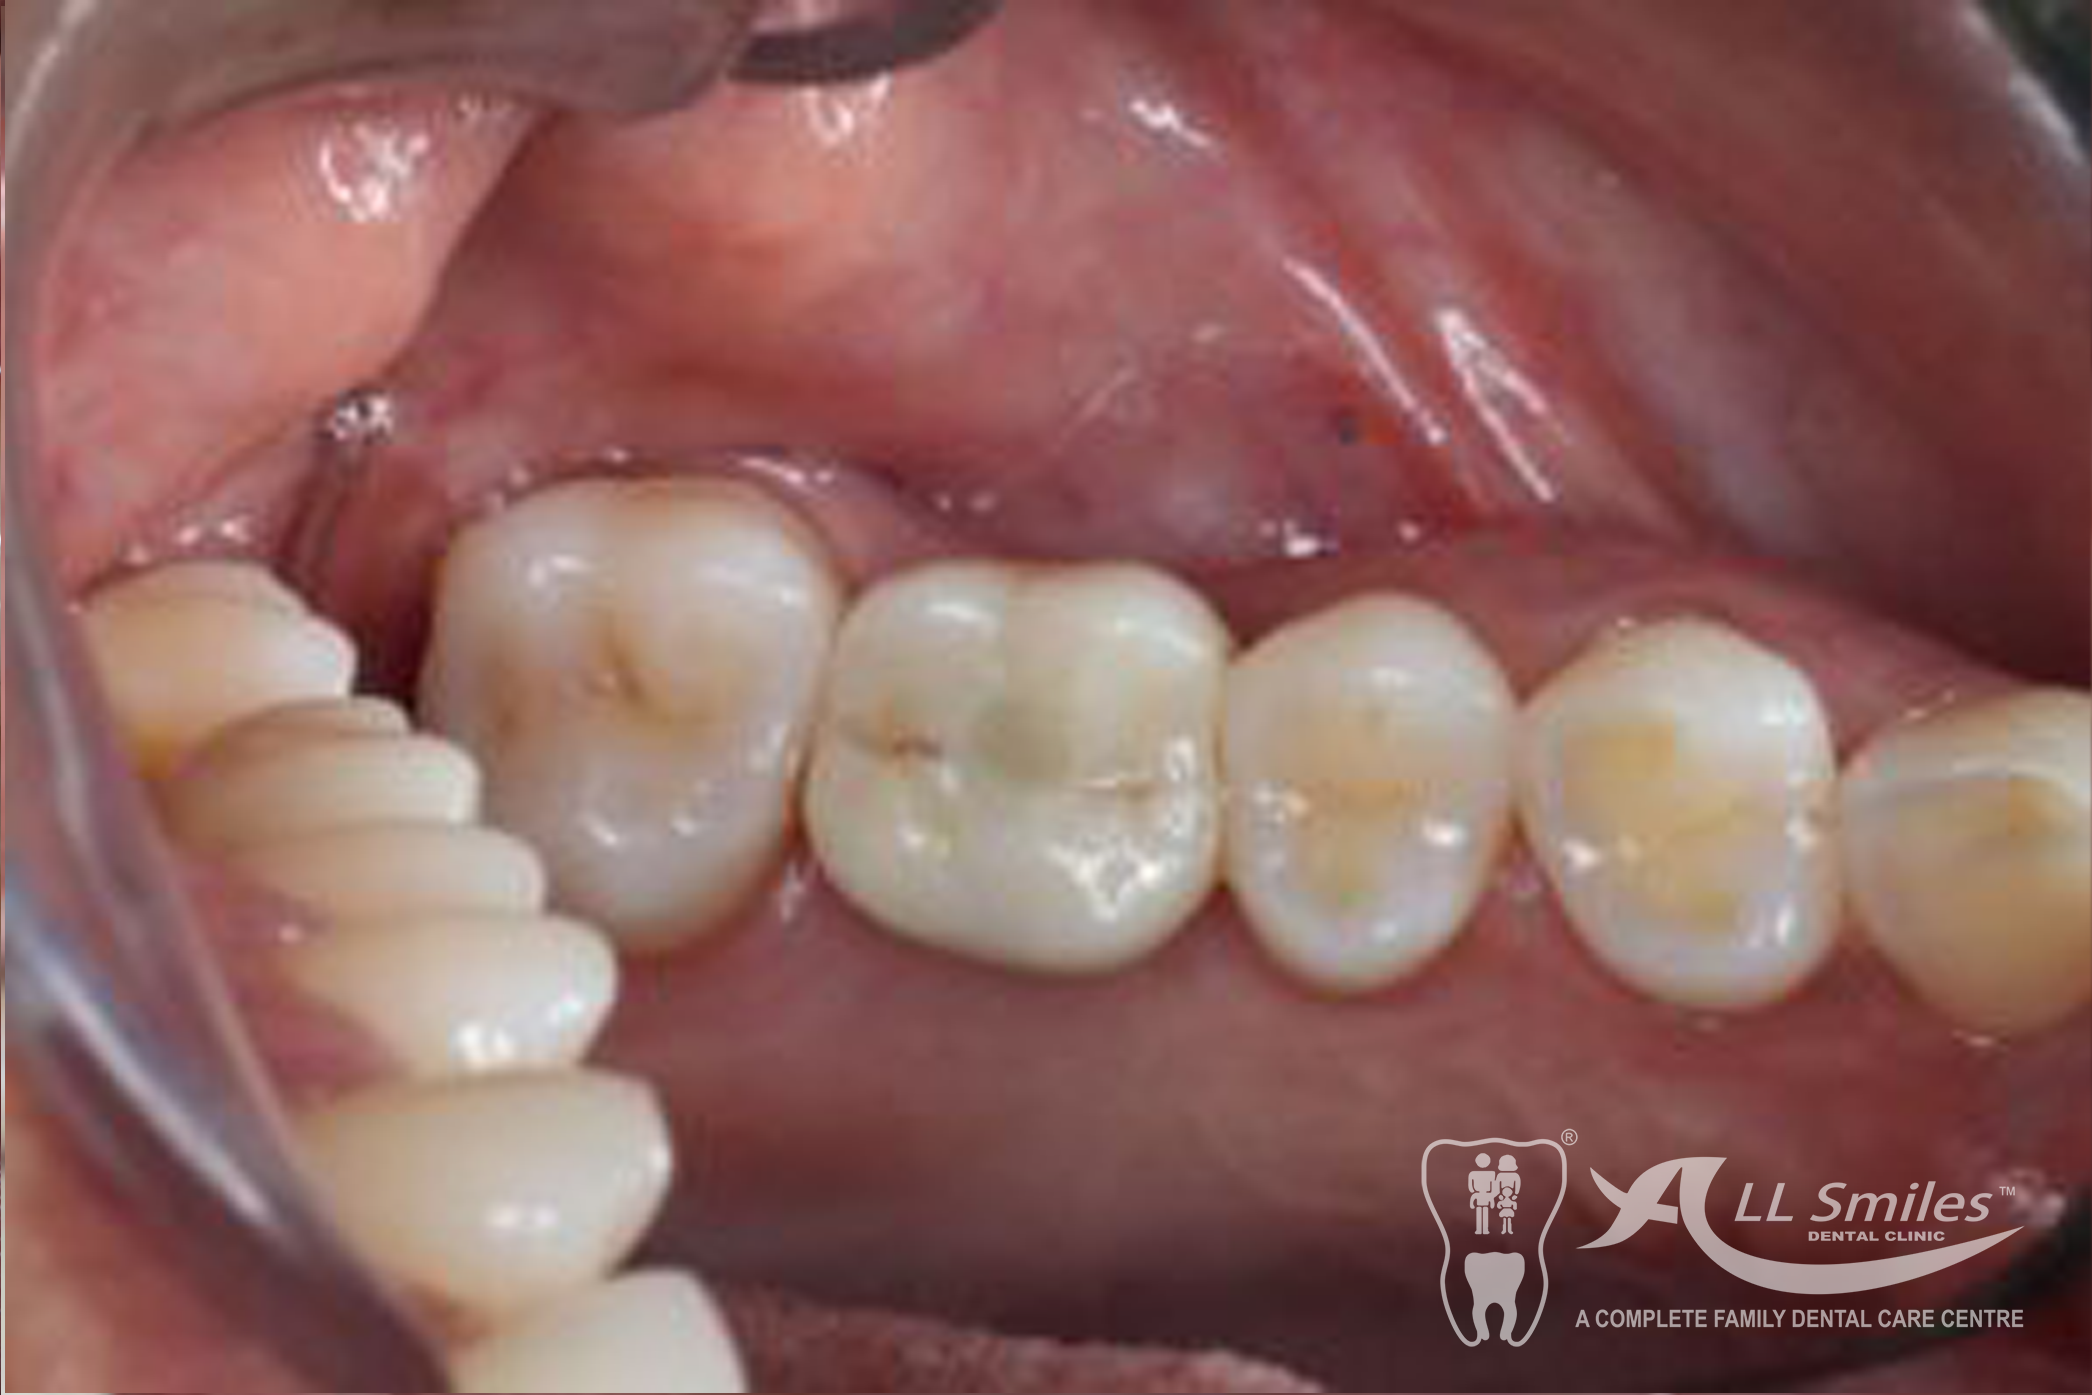

Implants For Multiple Missing or Broken Teeth Regardless of whether one or more teeth are missing in a row: Every tooth is individually replaced and the situation is restored to its original condition. If three or more teeth in a row are missing, you can decide to have an implant- borne bridge. In this solution the new crowns are linked together and depending on the size of the gap are placed on a stable and secure base of two or more implants .

After precise planning the new tooth roots are generally placed in the jaw in one single treatment session. A temporary denture closes the gaps during the healing phase. After healing the final crowns or the bridge are permanently fixed to the implants. Life With Bite! Dental Implants For The Edentulous Jaw.